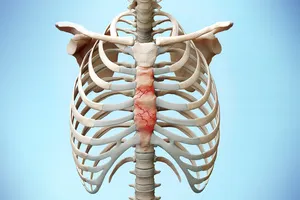

3. 늑골골절, 늑연골염

가슴 부위의 뼈나 여골, 특히 갈비뼈나 늑연골에 손상이 발생하면 통증이 나타날 수 있습니다. 숨을 쉬거나 몸을 움직일 때, 혹인 특정 부위를 누를 때 통증이 더욱 심해지는 것이 특징입니다. 충분한 휴식을 취하고, 진통소염제를 복용하며, 필요에 따라 물리치료를 받으면 증상 완화에 도움이 될 수 있습니다.

11. 갈비뼈 골절

갈비뼈 골절은 외부 충격으로 인해 흉곽을 보호하는 갈비뼈가 부러지는 것을 말합니다. 부러진 갈비뼈는 호흡할 때마다 심한 통증을 유발하며, 특히 기침이나 재채기를 할 때 통증이 더욱 심해지는 것이 특징입니다. 다행히도 대부분의 갈비뼈 골절은 보존적인 치료로 회복이 가능합니다. 진통제와 소염제를 복용하고, 충분한 휴식을 취하며, 통증이 심할 경우 팔을 베개로 받치고 옆으로 누워 휴식을 취하는 것이 좋습니다. 또한, 폐렴 예방을 위해 규칙적인 호흡 운동을 하는 것이 중요합니다.